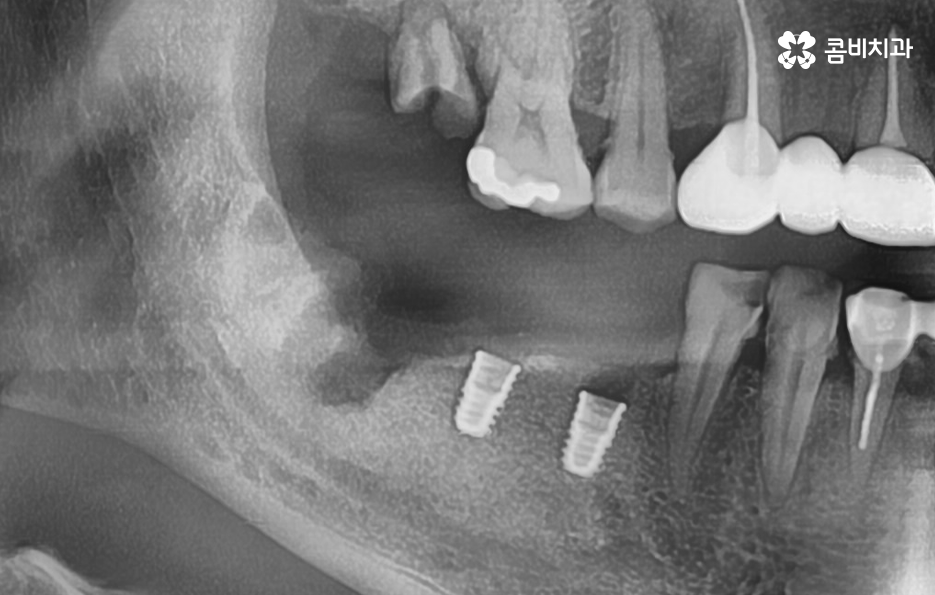

치아는 발치 후에 서서히 잇몸이 흡수되고 내려 앉게 되는데 이미 치아를 잃고 오랜 시간이 지난 분들의 경우에는 잇몸 뼈가 흡수되어 치조골 상태가 갈수록 얇아지고 내려앉은 상태일 수 있어요

또한 노년기에는 치주염으로 인해 치아를 잃게 되는 경우가 상당히 많은데 치주염으로 인해 잇몸 뼈가 녹은 경우에는 임플란트를 하기에는 잇몸 뼈가 부족하고 골질의 상태가 좋지 않은 경우도 많기 때문에 임플란트 치조골 상태를 건강하게 확보하기 위해 뼈이식을 진행할 수 있어요

임플란트 치조골 어떻게 뼈이식을 하면 될까요

앞서 설명드린 이유로 잇몸 뼈의 상태가 부족하신 분들의 경우에는 뼈이식을 추가적으로 진행하여 자신의 뼈처럼 단단하게 굳게 되면 일반적으로 건강한 잇몸 뼈를 가진 분들과 거의 동일하게 임플란트 수명이 유지된다고 보면 될 거예요

뼈이식이라고 하면 아무래도 어떤 뼈를 이식한다는 것인지 어렵게 느껴지기 쉬운데 일반적으로 치과 임플란트 뼈이식에 사용되는 뼈의 형태는 가루 상태의 뼈를 반죽 처럼 만들어서 잇몸 뼈에 이식한다고 이해하시면 되는데 뼈이식이라고 해서 통증이나 출혈이 더 심해지거나 그런 것은 아니기 때문에 너무 우려하실 필요는 없다고 볼 수 있어요